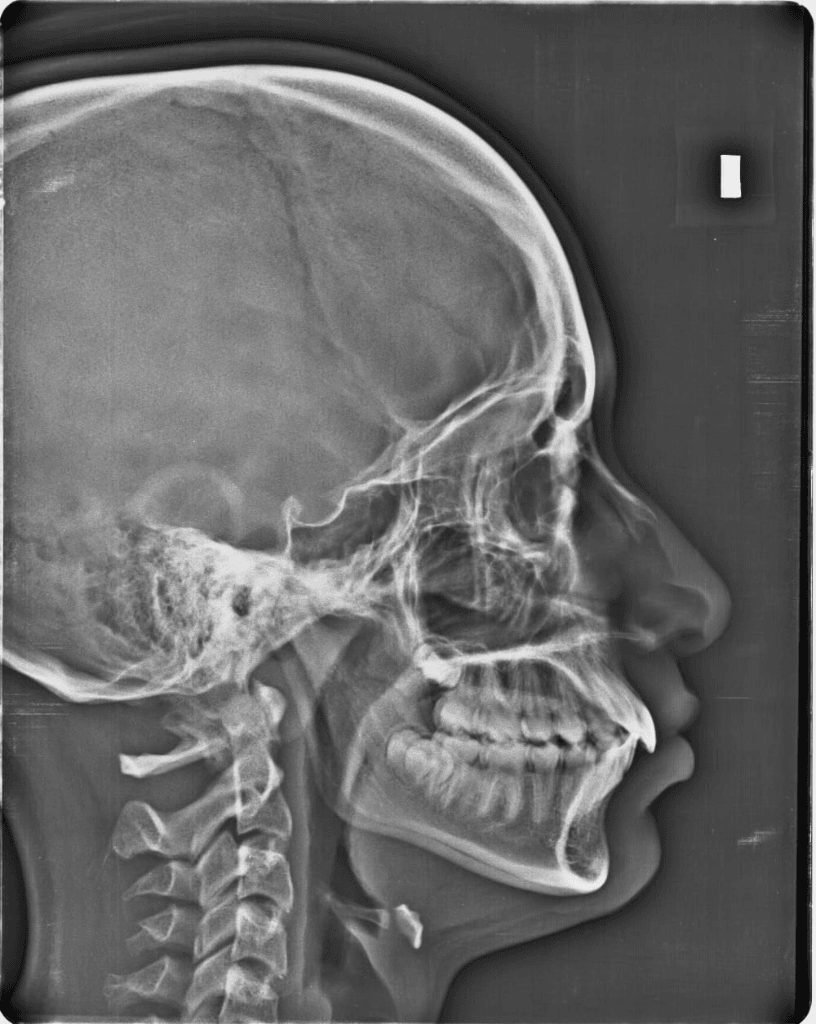

Essential 2D radiographs including panoramic and cephalometric dental x-rays, used for orthodontics, wisdom teeth, and general assessment.

Lateral skull X-ray for orthodontic analysis.

| Cephalometric Dental X-Ray (2D) | Lateral skull radiograph for orthodontic/surgical measurements. | $150 |